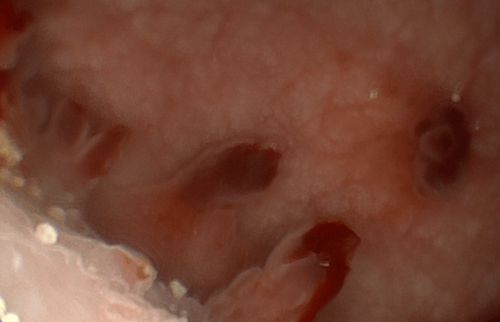

Entzündliche Veränderung der Schleimhaut mit sichtbaren Reizungen und Belägen (z. B. Ösophagitis).

Endoskopischer Befund von tiefen Schleimhautdefekten (Geschwüren/Ulzera) und entzündlichen Auflagerungen.